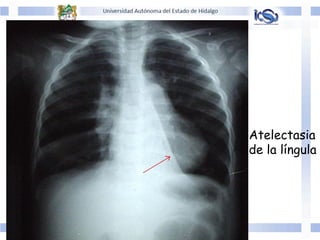

Atelectasia

de la língula